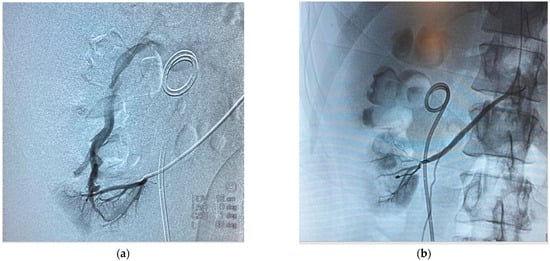

2. Case Report